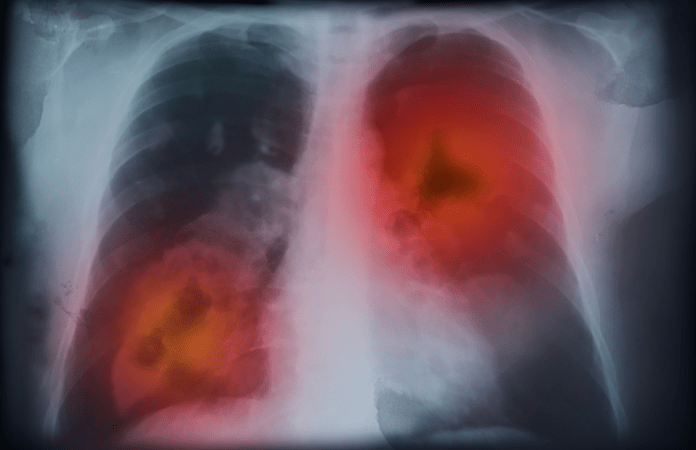

*El Grupo Español de Cáncer de Pulmón (GECP) alertó que la mortalidad por cáncer de pulmón sigue en aumento entre las mujeres impulsada por un incremento en su incidencia del 5,4% en la población femenina en España, según los últimos datos facilitados por el Instituto Nacional de Estadística (INE) en su informe ‘Defunciones según la causa de muerte.

Según este informe, las neoplasias de pulmón ya suponen la cuarta causa de muerte global en España y la primera por cáncer. Unos datos que preocuparon a los especialistas del GECP.

Tal y como explicó el experto, “nos enfrentamos a un problema sanitario de gran calado. Hay que volver a poner el foco en la lucha contra el cáncer, sobre todo en el de pulmón, que en la actualidad aglutina el 20% de todas las muertes. El total de fallecidos por esta causa en 2022 equivalieron a la suma de muertes de cáncer de mama, próstata y de colon en España”.

Así, cerca de 22.700 españoles perdieron la vida como consecuencia de un cáncer de pulmón en 2022, una mortalidad que permaneció estable en hombres (0%), pero que se incrementó un 5,4% en mujeres, respecto a 2021. La mortalidad absoluta en mujeres aumentó un 134% desde 2003.